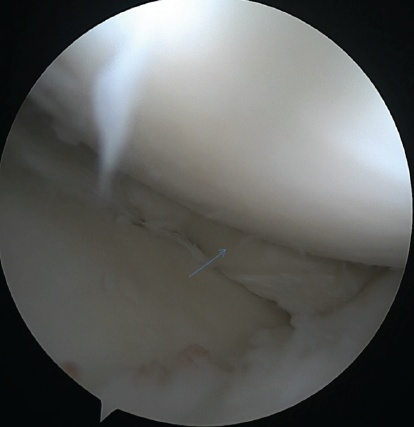

The medial fragment was displaced into the intercondylar notch; the lateral tear extended into the anterior horn. There was no tunnel widening. The reconstructed ACL graft appeared to be intact. However, the femoral tunnel is more vertical, indicating the trans-tibial technique for the graft placement. Arthroscopy was performed under spinal anesthesia with the patient in the supine position and under tourniquet. Standard anterolateral and anteromedial portals were used. During the first view of diagnostic arthroscopy, the displaced medial and lateral meniscus bucket-handle fragments with the intact ACL were visualized (Fig. 2). No cartilage changes were encountered.

Figure 2: Displaced both meniscus bucket handle tear in the center of the knee joint (right pointing arrow – displaced medial meniscus bucket handle tear, down arrow – displaced lateral meniscus bucket handle tear.